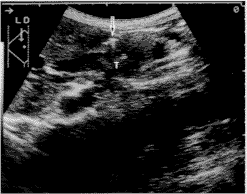

胆管癌对胰、十二指肠浸润的诊断率 当下段胆管肿瘤生长达壁层或壁外,浆膜面强回声增厚、模糊不清、中断,胆管肿瘤与胰腺分界不清,即为胰腺受侵的声像特征。观察判断浆膜是否受侵,对判断胰腺浸润状况意义重大。对照手术病理结果,超声对胰腺未受浸润(Pa1)14例的诊断正确率为71%。超声图像表现为浆膜清晰、规整、连续,肿瘤局限于管壁内(见图1)。病理镜下所见肿瘤未侵达浆膜。Pa1组4例超声表现胆管壁轻度均匀增厚,误判为Pa2。手术证实胰腺受侵(Pa2)18例超声诊断正确14例(见图2)。余4例Pa2中超声判为Pa1的有3例。即当肿瘤已突破部分浆膜,侵达胰腺组织时,超声图像仍可表现为浆膜增厚、未中断或完好。胰腺重度侵犯(Pa3)3例超声诊断正确率67%,余误为Pa2。根据诊断成绩,超声与手术病理分级完全一致26例,即胰腺浸润诊断正确率为74%。超声评判分级与病理不符或较病理分级低,可能与经腹超声的分辨率、周围胃肠气体影响有关。

图1 胆管下段低回声实性占位(T),肿瘤局限于管壁内。浆

膜(↓)规整,与胰腺(P)分界清。病理证实胰腺未浸润